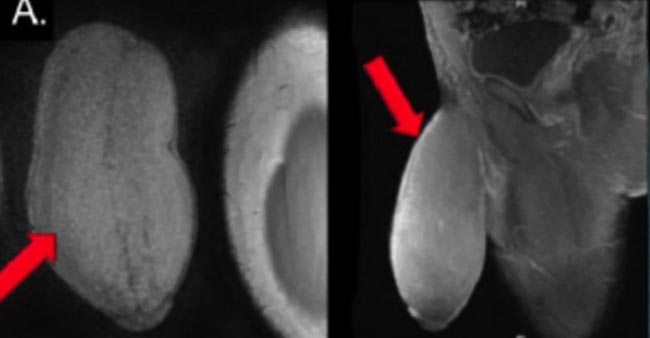

В спокойном состоянии длина пeниca подростка составляла 17,8 см в длину и целых 25,4 см в диаметре. С такими размерами половой орган подростка был больше похож на мяч для регби. Самое печальное во всем этом то, что во время эрекции пeниc не увеличивался в размерах, а оставался точно таким же.

Подростку разрезали кожу пeниca, отвернули её, вырезали боковые сегменты с обоих сторон и сшили кожу обратно.